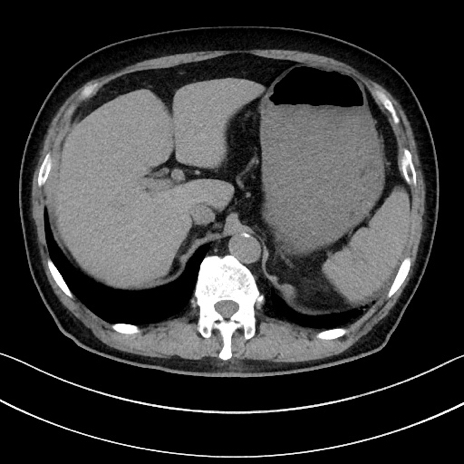

症例15(横断像)

【症例】70歳代男性

【主訴】腹痛

【現病歴】今朝から腹痛あり。全体的に痛い。特に左上の方。排ガスが今日はない。冷や汗が出る。

【既往歴】直腸癌術後

【身体所見】左側腹部〜上腹部に圧痛あり。腹膜刺激症状明らかなではない。軽度反跳痛。左下腹部に術後瘢痕あり。

【データ】WBC 7700、CRP 0.02